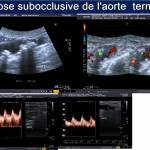

Il s’agit du cas typique d’une patiente présentant une sténose de l’aorte abdominale sous-rénale (sténose de l’aorte basse) à extension iliaque, découverte à l’occasion de la persistance de douleurs dorsales à irradiation fessière.

écho-Doppler artériel

Le diagnostic des thromboses aortiques présente une complexité notable, nécessitant une approche méthodique et l’utilisation de technologies d’imagerie avancées. Les thromboses aortiques, qui consistent en la formation de caillots sanguins dans l’aorte, peuvent entraîner des complications graves si elles ne sont pas identifiées et traitées rapidement. Les techniques diagnostiques les plus couramment employées incluent l’écho-doppler artériel et le scanner thoraco-abdominal injecté, chacune offrant des avantages uniques pour la détection des anomalies vasculaires.

L’écho-doppler artériel est souvent la première étape dans l’évaluation des thromboses aortiques. Cette technique utilise des ultrasons pour visualiser le flux sanguin et détecter toute obstruction ou anomalie dans l’aorte. L’écho-doppler permet non seulement de confirmer la présence d’une thrombose mais aussi d’évaluer sa taille et son emplacement précis. Toutefois, cette méthode peut être limitée par la qualité de l’image obtenue, surtout chez les patients ayant une anatomie complexe ou de l’athérosclérose avancée.